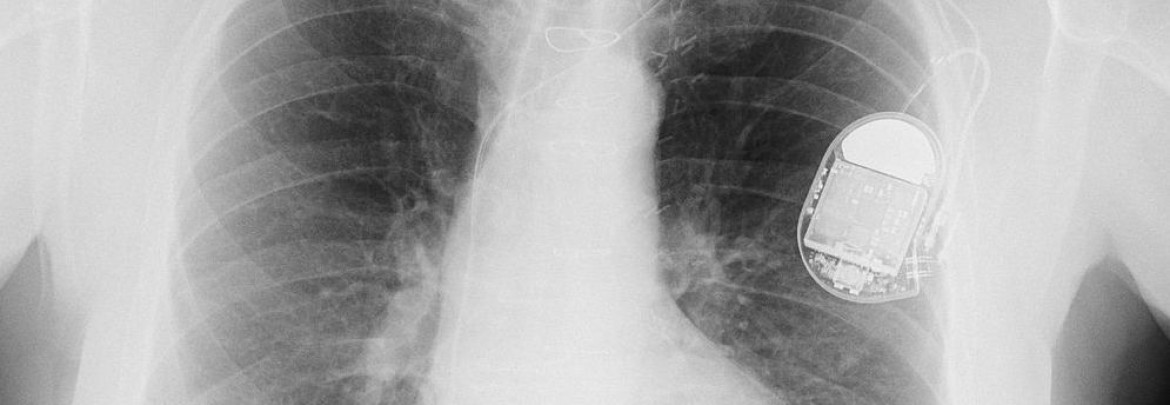

pacemaker

Provides evaluation and ongoing follow-up for patients with implanted pacemakers and defibrillators to ensure each device is working properly and to monitor the life of the device.